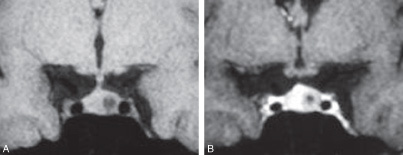

Voici une IRM coupe frontale T1, avant et après injection de gadolinium, passant par la selle turcique: quel diagnostic?

micro-adénome hypophysaire (moins de 1 cm)

noter la prise contraste plus lente que le reste de l’hypophyse et la rétention du produit